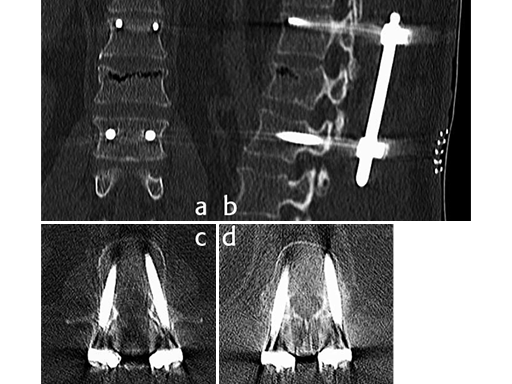

Using the USS Fracture MIS system for the initial stabilization allowed for a minimally invasive approach with intraoperative active reduction of the spinal fracture. The unique design of the fracture clamp allowed for independent correction of the sagittal alignment (Fig a) as well as height readjustment (Fig b).

Follow up CT Scans (AP, lateral and coronal) after the second surgery.